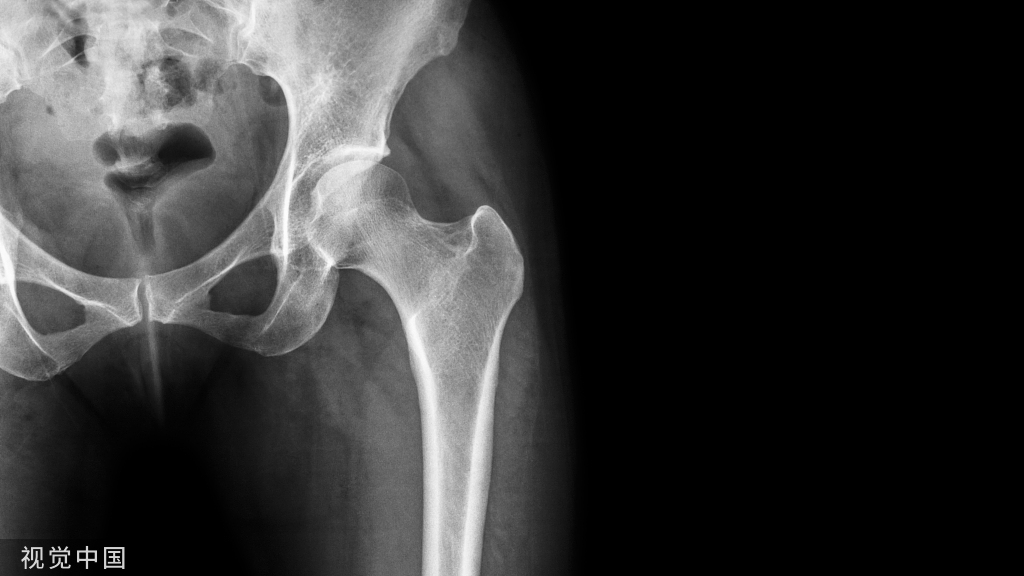

我们先要了解一下具体的解剖。

由于桡骨远端存在掌倾角,桡骨远端掌侧存在一个分水岭。背侧剪切损伤表现为背侧边缘骨折,并且通常与腕骨的背侧不稳定相关。这些损伤通常有凹陷的关节碎片,并可能有额外的桡柱受累。掌侧剪切损伤表现为掌侧边缘移位骨折并导致腕骨掌侧不稳定。这种模式通常具有多个关节碎片并且高度不稳定。桡骨剪切性骨折(驾驶员骨折)通过穿过桡骨茎突,延伸到桡腕关节的特征性横向骨折线来识别。这三类,都属于极远端骨折